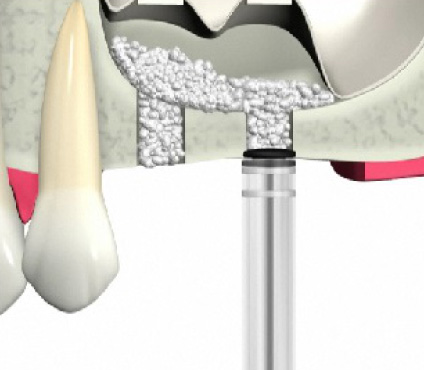

ソケットリフト方法

歯肉を切開します。

骨をドリルで切削します。

上顎洞の壁を押し上げます。

骨の材料を充填します。

インプラントを埋入します。

歯槽骨が吸収し、上顎洞が下がっています。このままではインプラントが突き抜けてしまうためインプラントはできません。

上顎洞が上に押し上げられ、インプラントを埋入するスペースができました。骨の材料も充填されているのでインプラントは安定します。